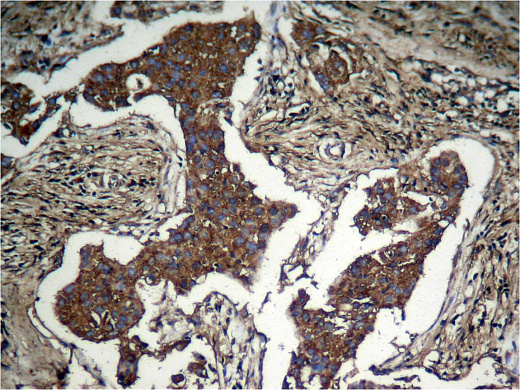

• применение – ICC/IF, IHC-P, WB;

Akt, также известная как протеинкиназа B (PKB), представляет собой серин/треонин-специфическую протеинкиназу, которая играет ключевую роль в клеточных процессах, таких как метаболизм глюкозы, апоптоз, пролиферация клеток, транскрипция и миграция клеток. AKT может фосфорилироваться комплексом mTOR 2 (mTORC2) и ДНК-зависимой протеинкиназой (DNA-PK) по остатку Serine 473 (Ser473).